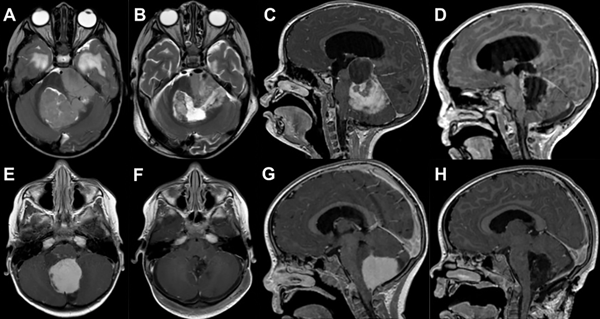

El grado de resección se categorizó como resección total (gross total resection, GTR), resección subtotal (sub-total resection, STR) y resección parcial (partial resection, PR), basado en la observación intraquirúrgica y de imágenes de RMI postoperatorias (hasta 72 horas posteriores a la cirugía). GRT correspondió a la ausencia de restos tumorales en RMI concordante con la apreciación intraquirúrgica de los neurocirujanos. STR correspondió a los casos en los que se observó un resto tumoral menor al 5% en RMI o intraoperatorios como en los casos de invasión del tronco encefálico. PR, cualquier grado de resección que no cumplió los criterios anteriores (Figura 1).

Figura 1: Análisis comparativo de imágenes de resonancia magnética (RM) prequirúrgicas y postoperatorias, destacando los distintos grados de resección tumoral.

A y B: imagen axial de RM ponderada en T2 en el que se observa una lesión correspondiente a Ependimoma Anaplásico de fosa posterior y su resección parcial (PR) debido a la adherencia de la misma a la cara lateral del tronco encefálico.

C y D: imagen sagital de RM ponderada en T1 con gadolinio en la que se evidencia una lesión sólido-quística en fosa posterior, compatible con Astrocitoma pilocítico y la resección subtotal (STR) con un resto en región de la cisterna cuadrigeminal que se encontraba adherido.

E, F, G y H: Imágenes axiales y sagitales de RM ponderadas en T1 con gadolinio, de un paciente con lesión en fosa posterior compatible con Astrocitoma de fosa posterior y su resección completa (GTR).